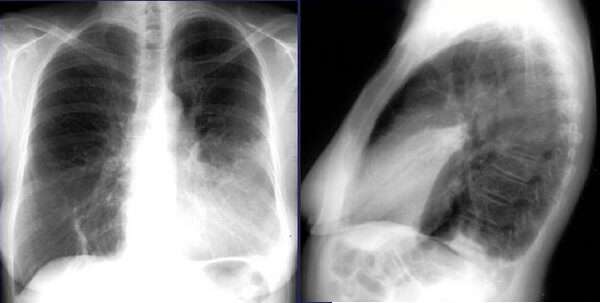

По мере прогрессирования патологии на рентгенограмме грудной клетки видна инфильтративная тень с нечеткими контурами.